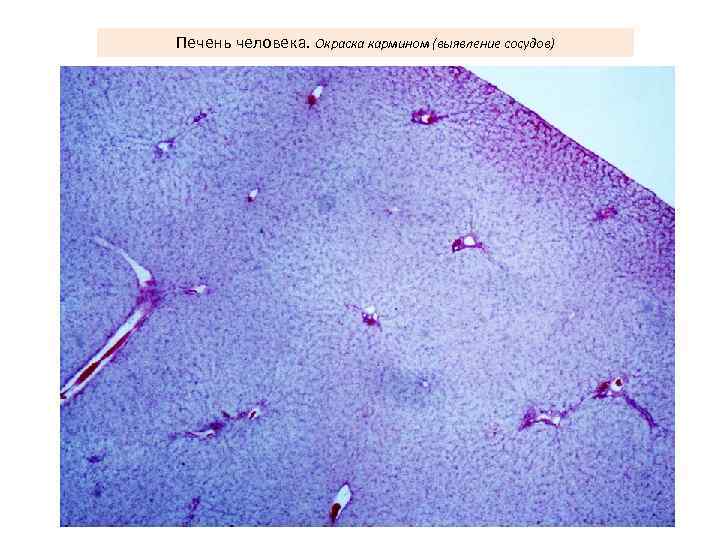

Печень человека. Окраска кармином (выявление сосудов)

Центральная вена и синусоидные капилляры